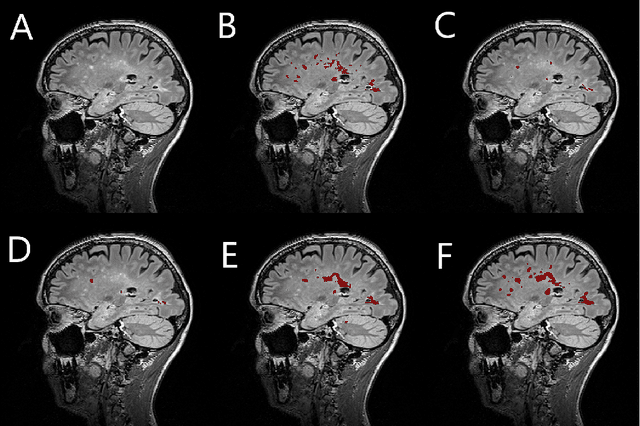

Abstract:The detection of new or enlarged white-matter lesions in multiple sclerosis is a vital task in the monitoring of patients undergoing disease-modifying treatment for multiple sclerosis. However, the definition of 'new or enlarged' is not fixed, and it is known that lesion-counting is highly subjective, with high degree of inter- and intra-rater variability. Automated methods for lesion quantification hold the potential to make the detection of new and enlarged lesions consistent and repeatable. However, the majority of lesion segmentation algorithms are not evaluated for their ability to separate progressive from stable patients, despite this being a pressing clinical use-case. In this paper we show that change in volumetric measurements of lesion load alone is not a good method for performing this separation, even for highly performing segmentation methods. Instead, we propose a method for identifying lesion changes of high certainty, and establish on a dataset of longitudinal multiple sclerosis cases that this method is able to separate progressive from stable timepoints with a very high level of discrimination (AUC = 0.99), while changes in lesion volume are much less able to perform this separation (AUC = 0.71). Validation of the method on a second external dataset confirms that the method is able to generalize beyond the setting in which it was trained, achieving an accuracy of 83% in separating stable and progressive timepoints. Both lesion volume and count have previously been shown to be strong predictors of disease course across a population. However, we demonstrate that for individual patients, changes in these measures are not an adequate means of establishing no evidence of disease activity. Meanwhile, directly detecting tissue which changes, with high confidence, from non-lesion to lesion is a feasible methodology for identifying radiologically active patients.

Abstract:Segmentation of both white matter lesions and deep grey matter structures is an important task in the quantification of magnetic resonance imaging in multiple sclerosis. Typically these tasks are performed separately: in this paper we present a single CNN-based segmentation solution for providing fast, reliable segmentations of multimodal MR imagies into lesion classes and healthy-appearing grey- and white-matter structures. We show substantial, statistically significant improvements in both Dice coefficient and in lesion-wise specificity and sensitivity, compared to previous approaches, and agreement with individual human raters in the range of human inter-rater variability. The method is trained on data gathered from a single centre: nonetheless, it performs well on data from centres, scanners and field-strengths not represented in the training dataset. A retrospective study found that the classifier successfully identified lesions missed by the human raters. Lesion labels were provided by human raters, while weak labels for other brain structures (including CSF, cortical grey matter, cortical white matter, cerebellum, amygdala, hippocampus, subcortical GM structures and choroid plexus) were provided by Freesurfer 5.3. The segmentations of these structures compared well, not only with Freesurfer 5.3, but also with FSL-First and Freesurfer 6.1.